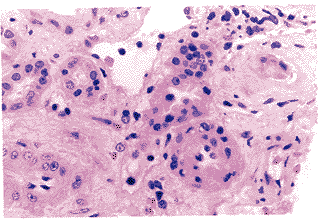

光镜下所有32个肾小球均呈现纤维性新月体,新月体挤压毛细血管袢,使袢闭锁,仅个别球见少数袢开放。囊壁增厚、分层,囊外纤维化明显。PASM-Masson染色见肾小球基底膜节段双轨,未见免疫复合物沉积。小管间质病变重,弥漫性小管基膜增厚、萎缩,少数小管腔囊样扩张,内见巨大蛋白管型,多处见钙化。间质区域增宽明显,有弥漫的单个核细胞浸润。动脉管壁增厚,有的见炎细胞浸润,未见坏死性病变(图4,见插页图)。免疫荧光检查仅见IgG+,C3++颗粒状沉积于系膜区及血管袢。

图4A 肾小球纤维素性环状新月体,血管袢被挤压(PAS,×400)

图4B 间质小动脉较多单个核细胞浸润(HE,×400)